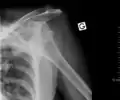

| Anterior dislocation of the left shoulder. | |

An anterior dislocation of the shoulder